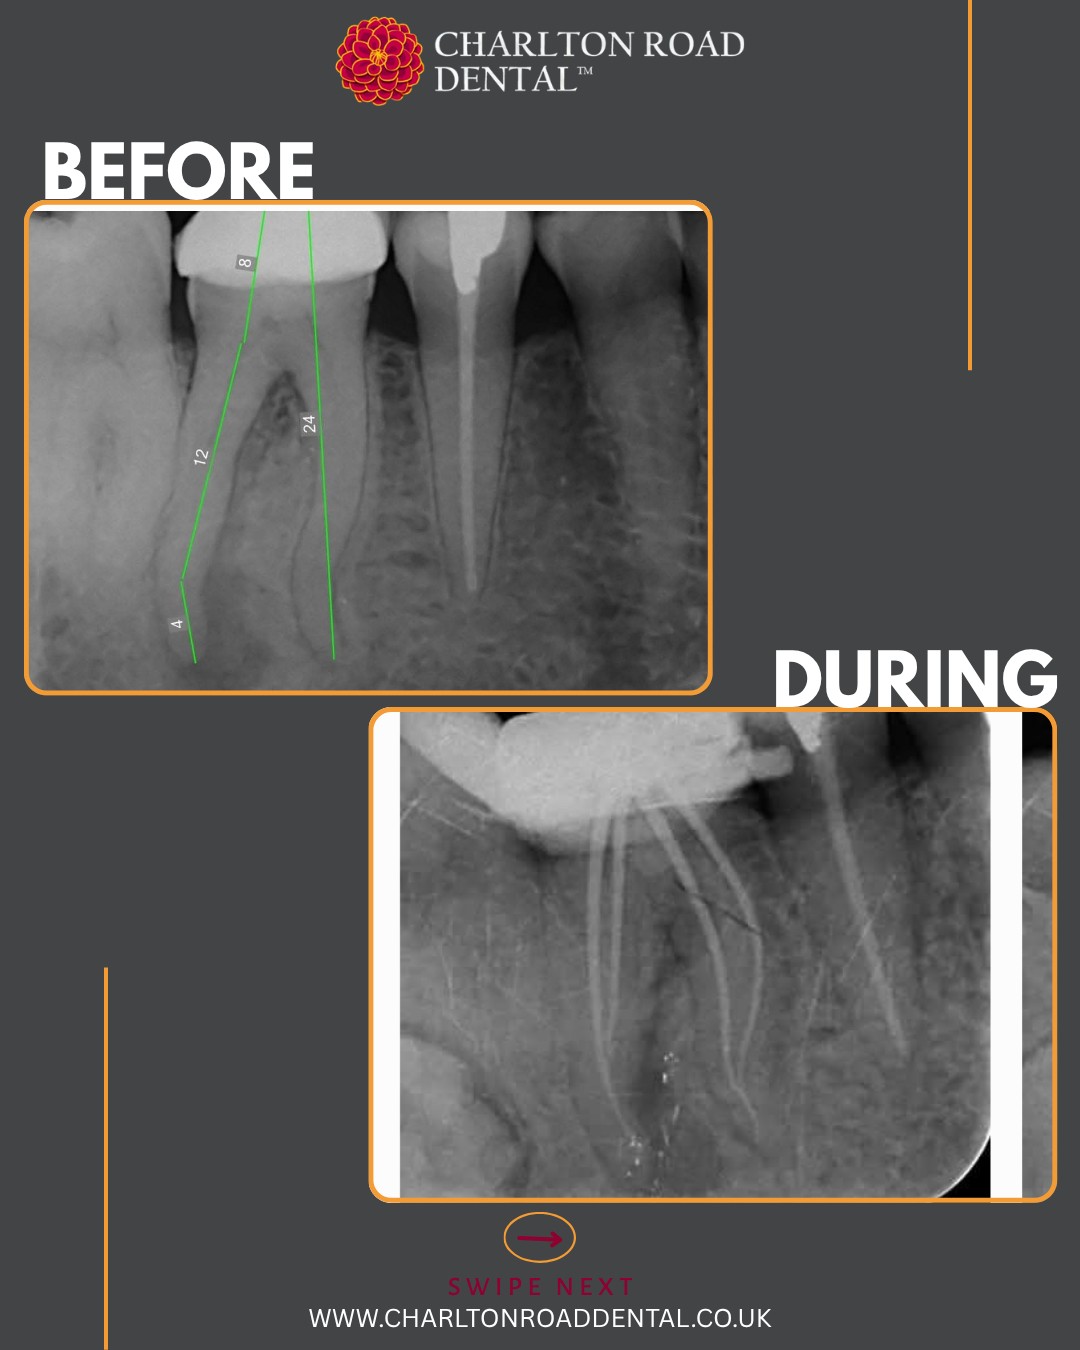

A complex RCT case by Dr. Adrian Jones

S-shaped curves in molar canals are ideal for putting the VS Flexi Blue files to the test. These files offer excellent flexibility and allow for conservative shaping of the canals, thereby preserving precious tooth structure.

First up: a UL6. Periodontal treatment has been completed and stabilised. This was a necrotic case with a history of an acute flare-up a few months ago. I used the existing filling as a reference to help orient the access cavity. Numerous pulp stones were encountered.

I prepared the DB and palatal roots first, allowing the MB root to soak in disinfection solution in the meantime. I instrumented the MB root system up to size 20/06, and up to 25/06 in the palatal and DB roots. Irrigation was performed using full-strength sodium hypochlorite and Endo solution, delivered with Irriflex tips. I used a yellow EndoActivator for agitation and micro-suction to dry the canals.

Total Fill sealer was placed and carried to working length using a size 25/029 gutta-percha point. I customised a size 20/029 GP point for the MB root, a 25/029 GP point for the DB root using a taper plate, and used a master fit GP point for the palatal root. The tooth was then sealed with LuxaCore.